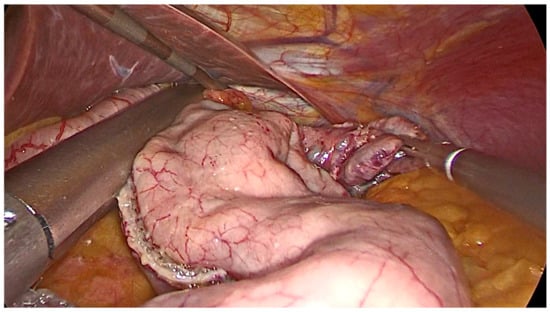

- Opening a window in the gastro-colic ligament using an energy device from the antrum and proceeding up to the angle of His, along the greater curvature, until the left diaphragmatic pillar was fully exposed.

- The gastric fundus must be entirely mobilized with coagulation and section of the short gastric vessels and the opening of the gastro-splenic ligament.